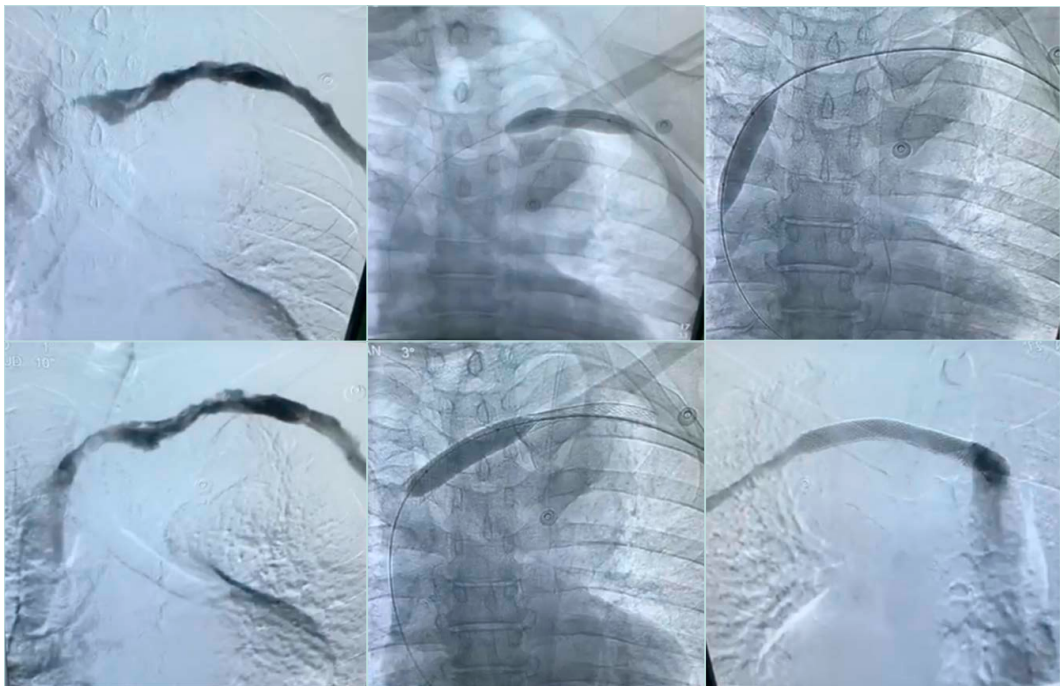

Catheter-directed thrombolysis (CDT) : This technique involves infusion of tissue plasminogen activator (tPA) via multi-side-hole catheter inserted within the thrombus over 12 to 24 hours. During this time, the patients require one-on-one care in a high dependency unit (HDU) or intensive treatment unit (ITU) bed (Figures 8 and 9).

Figure 8. Initial venogram shows thrombosed axillary-subclavian vein (left image), selective venogram beyond the thrombus (middle image), and fluoroscopic picture confirming location of the tip of the infusion catheter distal to the thrombus (right image).

After thrombus removal, immediate completion venography with or without IVUS is recommended to confirm the flow restoration; detect any residual webs, stenosis, or intimal hyperplasia; and to guide decisions about the need for additional decompression or revascularization procedure (Figure 10).